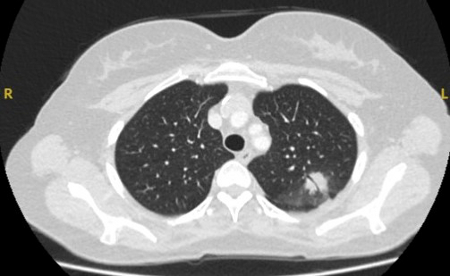

Computed tomography (CT) showing a posterior left upper lobe spiculated nodule, with ‘bronchus sign’ in a female non-smoker. Bronchoscopic forceps biopsy and brushing assisted by radial EBUS miniprobe localisation, confirmed a non-Hodgkin’s lymphoma

From the collection of Dr George Tsaknis, MD, PhD, FRCP(London), MRQA, MAcadMEd, PGCert; used with permission